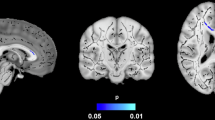

The trajectory of BMI with age was different in the case group compared with the control group (Fig. 2A). Those with dementia had higher BMI at 60 years and accelerated decline in later life. The BMI declined more slowly with age for those without dementia and was higher than demented patients after 78 years. The trajectory of WC (Fig. 2B) with age was similar to that of WtHR (Fig. 2C), which increased in mid-life and declined in later life. The changes of trajectories between cases and controls were close to that of BMI. Those with dementia had higher WC and WtHR in mid-life but experienced accelerated decline with aging, which was lower than the control group at 76 years and 80 years. Details of all mixed effect models for the trajectories were in Supplementary Table 3.

A Trajectory of BMI with age in the dementia group (cases) compared with the non-dementia group (controls). B Trajectory of waist circumference with age in the dementia group (cases) compared with the non-dementia group (controls). C Trajectory of waist-to-height ratio with age in the dementia group (cases) compared with the non-dementia group (controls). Trajectory of adiposity measures with age by dementia (cases) and non-dementia (controls) *Bands indicate 95% CI. BMI body mass index. **Baseline age, sex, education, year of inclusion, and follow-up duration were matched. ***Due to very few cases, trajectories were fitted only for those aged over 60 at baseline to avoid overfitting.